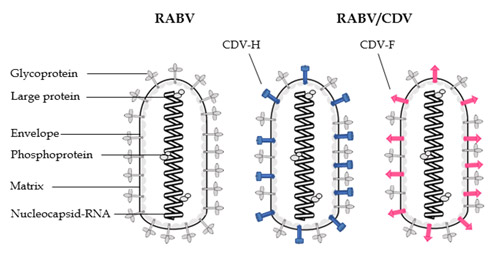

Prof. Dr. Veronika von Messling's group at the Veterinary Medicine Division, Paul-Ehrlich-Institut, in collaboration with Dr. Matthias Schnell's group at Thomas Jefferson University genetically engineered the rabies virus vaccine strain to carry one of the canine distemper virus glycoproteins in addition to its own glycoprotein. The protective immune response is directed against these proteins. Candidate vaccines were then produced following the purification and inactivation protocols used for rabies vaccines.

The researchers first demonstrated that a single shot was sufficient to elicit protective rabies antibody titers in ferrets. However, protection against canine distemper was only achieved when animals were immunized with a mix of viruses carrying both canine distemper virus glycoproteins. The researchers conclude that immune responses against both glycoproteins are necessary to protect from canine distemper.

Rabies virus (left) was genetically modified to carry either the canine distemper virus H protein (middle, shown in blue) or F protein (right, shown in pink) on its surface.

Rabies virus (left) was genetically modified to carry either the canine distemper virus H protein (middle, shown in blue) or F protein (right, shown in pink) on its surface.